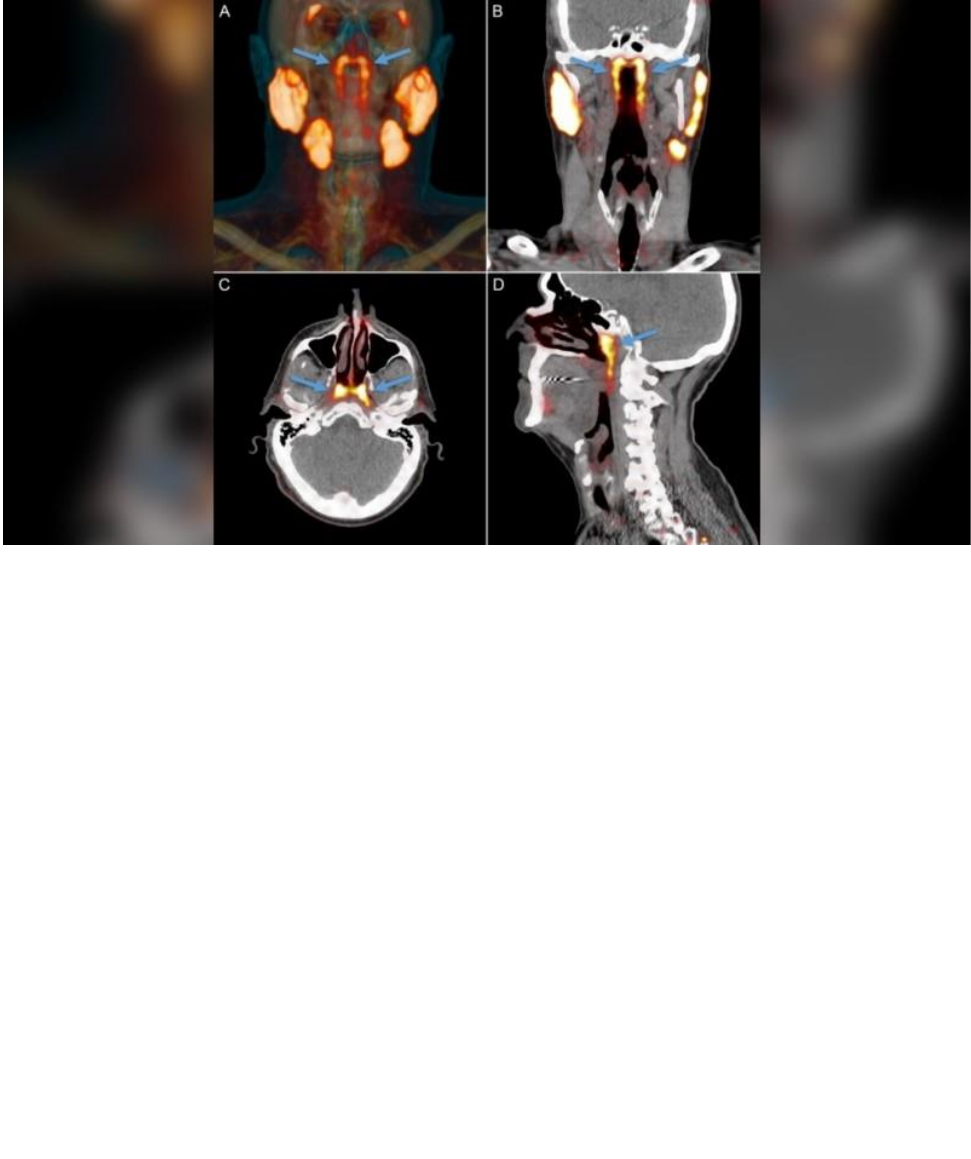

A imagem mostra o novo conjunto de glândulas encontradas por pesquisadores

enquanto procuravam células de câncer de próstata usando uma combinação de

tomografia computadorizada e tomografia por emissão de pósitrons chamada

PSMA PET-CT.